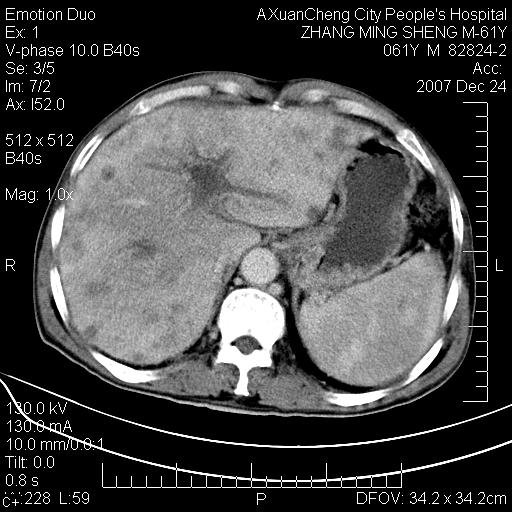

标题: CT11031:M61Y,胰腺占位

大家侃侃门静脉和胆管系统怎么回事,肝内转移?

胰腺癌肝转移

肝硬化,门脉高压,脾肿大;弥漫性肝癌,肝内、门脉、腹膜后淋巴结转移,肝内外胆管扩张,胰头区占位,建议mr检查

胰腺癌伴肝内转移;门脉、肠系膜上v癌栓形成。

考虑为:胰腺癌伴肝脏转移、腹膜后淋巴结转移,门静脉及肠系膜上静脉瘤栓形成。

胰体尾癌伴肝内转移,门静脉及肠系膜上静脉瘤栓形成.